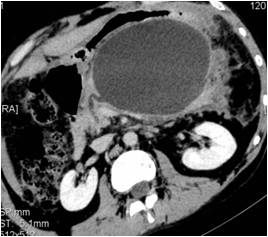

Contrast MRI with MRCP |

Cyst wall nonenhancing Main pancreatic duct – cyst communication present (Figure 4) |

Figure 4. Main pancreatic duct – cyst communication present